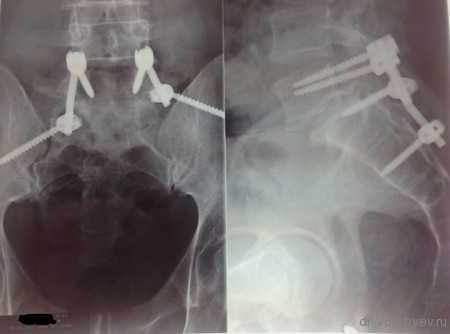

Рентген послеоперационной перкутанной ТПФ у пациентки с множественными переломами позвоночника

Пациенту по поводу спондилолизного спондилолистеза выполнена декомпрессия и позвоночно-тазовая стабилизация системой expedium

Рентгеновского снимка после операции